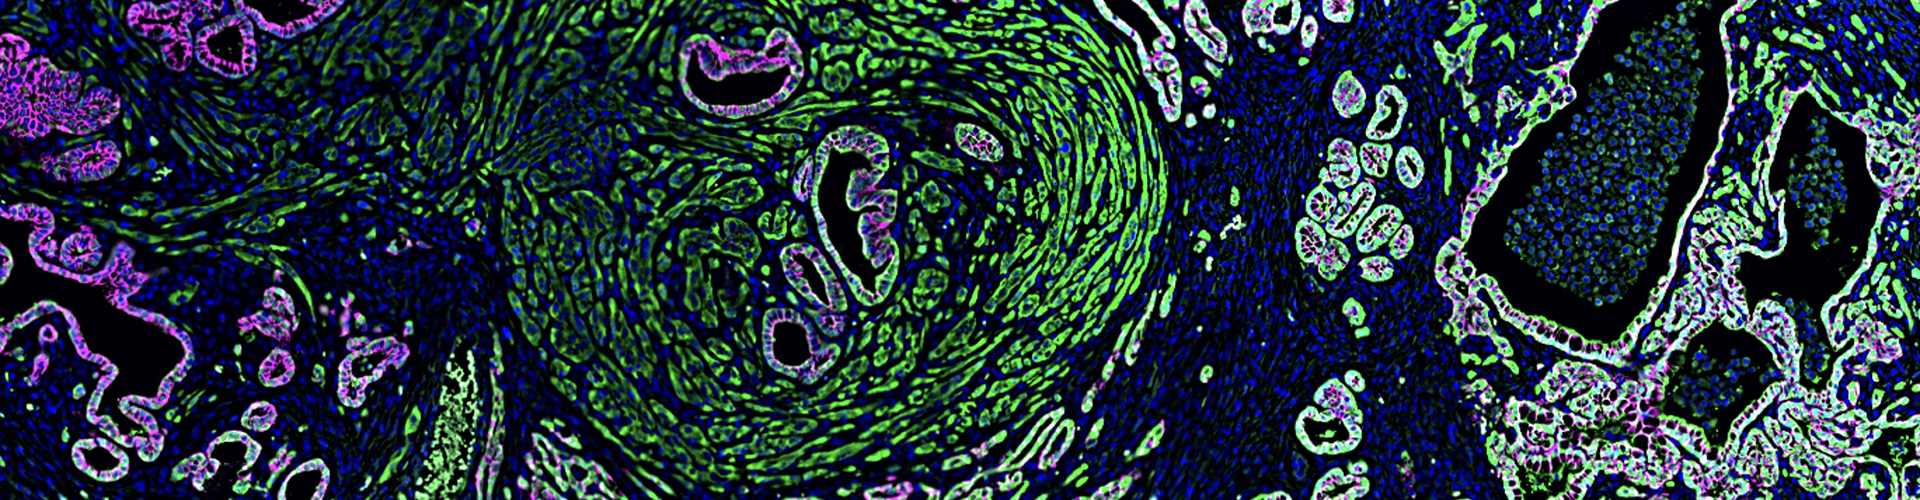

• Understanding mechanisms of cellular plasticity that facilitate metastasis

• Mechanism of epithelial-to-mesenchymal transition (EMT)

• Building novel genetically engineered mouse models to study epithelial plasticity and squamous/basal/quasimesenchymal subtypes in pancreatic cancer progression